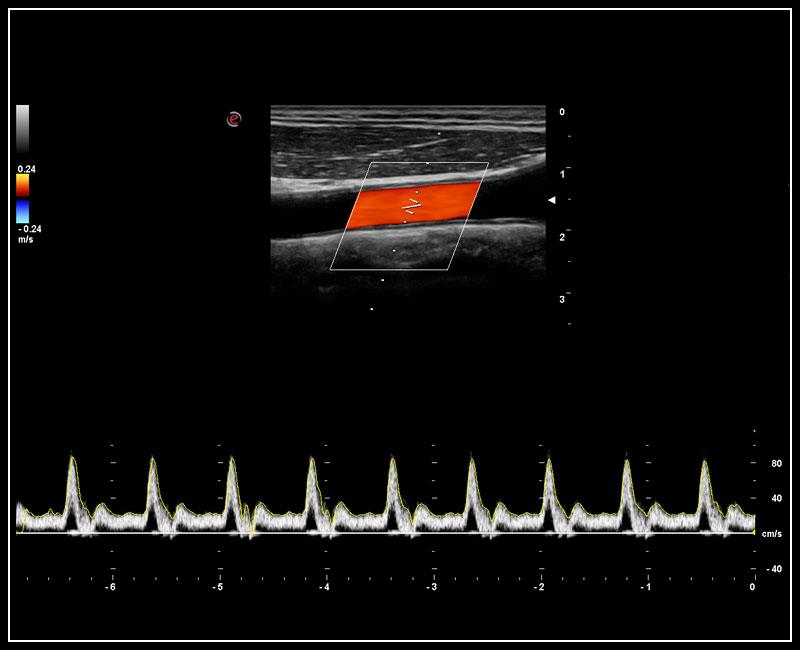

XFlow – Tăng cường độ nhạy trong siêu âm mạch máu, đặc biệt là các mạch máu nhỏ, có vận tốc thấp.

TVM - Bản đồ vận tốc mô với chế độ kép (Doppler màu và Doppler năng lượng).